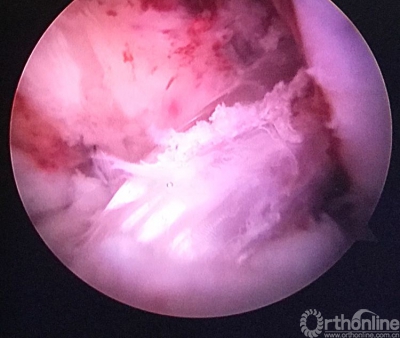

重建后关节镜检查见ACL的走向及张力等均好。

关节镜从前内入路进入,清晰的见到原胫骨隧道内口与返修后的相距较远。

返修手术后检查患者的膝关节前抽屉试验(-),Lachman(-)。